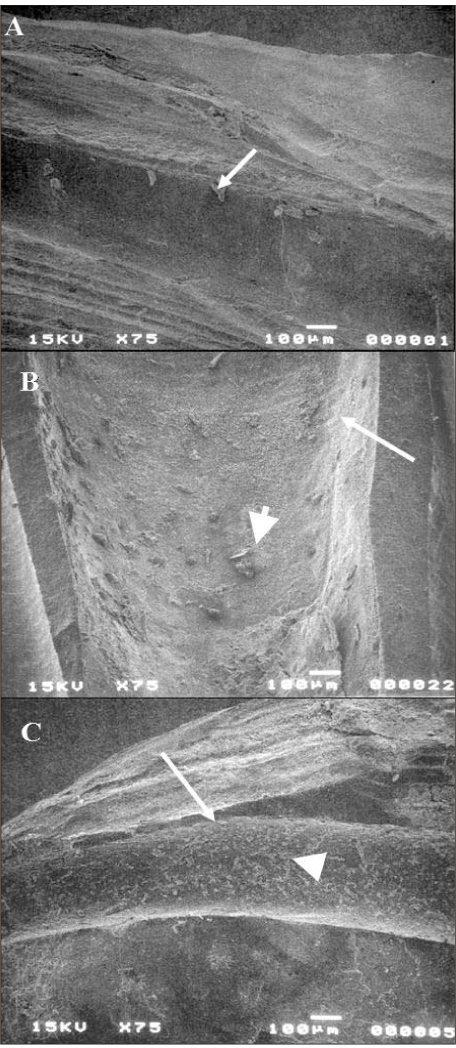

Figure 1

SEM pictures of sectioned roots after Resilon was removed by ProFiles.

Arrows indicate the root canal wall and arrow heads indicate the debris after retreatment. A : Middle portion of root canal wall revealed a clean surface after Resilon filling was removed (score 2). B : Coronal part of root showed multiple sealer debris (score 3). C : Apical root canal wall showed an unclean surface with debris (score 4).

The results for root canal cleanliness are summarized in Table 1. There was no significant difference between the two experimental groups. Generally most of the specimens demonstrated clean surface with small amount of sealer. More debris remained in the apical and middle thirds than in the coronal part. The openings of dentinal tubules were detected under higher magnifications in both experimental groups (Figure 2). However, dentinal tubules were not always patent. More smear layer was observed in the apical root wall (Figure 1).